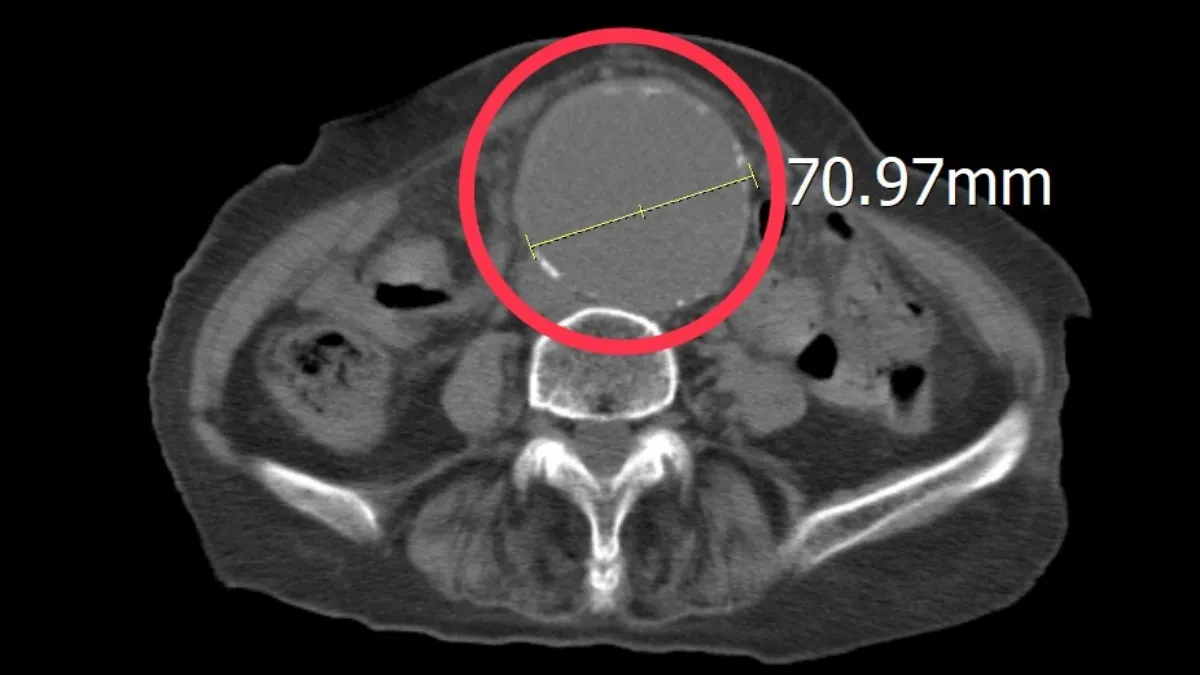

該名高齡患者在家人陪同下送至平等澄清醫院急診,患者自訴左側下肢與腰部極度不適,疼痛指數高達8至10分的重度疼痛,且無明顯外傷史。急診醫師孫秀正隨即為其進行床邊超音波檢查,影像顯示患者腹主動脈明顯擴張,直徑已突破7公分大關。隨後經由電腦斷層掃描進一步確認,診斷為大型腹主動脈瘤。由於血管壁已因硬化與退化變得極其脆弱,宛如體內的「不定時炸彈」,隨時有破裂引發大量出血的風險。

該名患者的動脈瘤已達7公分,處於隨時可能破裂的極高危險狀態。所幸及時發現並啟動跨科會診,迅速轉送中港院區接受手術治療,成功把握黃金期,術後恢復良好,目前已康復出院。